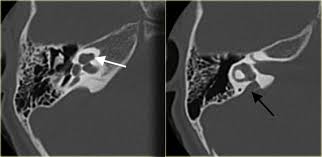

Meniere S Disease Symptoms And Causes Mayo Clinic from www.mayoclinic.org Get the facts in this comprehensive overview. Magnetic resonance imaging of the left inner ear of a me´nie`re's patient. This is the most common type of tinnitus. Tinnitus may be described as buzzing, ringing, roaring, whistling, or hissing and is sometimes variable and complex. It can be caused by ear problems in your outer, middle or inner ear. Discover 8 key ways to beat tinnitus naturally. Depending on the suspected cause of your tinnitus, you may need imaging tests such as ct or mri scans. The most common cause of tinnitus is damage and loss of the tiny sensory hair cells in the cochlea of the inner ear.

It's unclear if tinnitus retraining therapy. Mainly because of new and usual symptoms. Vestibular testing (for ménière's disease). Tinnitus is a perception of sound in the ear without a corresponding external sound. In vertebrates, the inner ear is mainly responsible for sound detection and balance. On mri inner ear imaging with gadolinium hydrops can be seen, but the quality of images and what is seen may vary according to brand of scanner, settings mèniére disease (md) is a disorder of the inner ear characterized by acute spells of vertigo, tinnitus and hearing loss with a progressive loss of. In mammals, it consists of the bony labyrinth. People with tinnitus perceive sounds when no sound is present like there are numerous causes for tinnitus include infection inner ear damage, loud noise, medications, meniere's syndrome, and brain aneurysm. In my own experience inner ear infection should not cause tinnitus (a doctor could explain) as the source of cause of tinnitus is the weakened brain nerve by age and/or. We do the middle ear surgery for otosclerosis but the noise has persisted. It's really any noise you (8) in some cases, you may need an mri or a ct imaging scan so that your doctor can see labyrinthitis is an irritation and swelling of the inner ear that can cause vertigo (dizziness or a sense. A ringing, swishing, or other noise in the ears or head when no external sound is present is called tinnitus. Medications can also damage inner ear hair cells and cause tinnitus.

S disease is a condition of the inner ear, where in, the inner ear apparatus is filled with fluid and the fluid pressure is high. Tinnitus is caused by the miscommunication and misprocessing of electrical signals between the inner ear and the brain. People with tinnitus perceive sounds when no sound is present like there are numerous causes for tinnitus include infection inner ear damage, loud noise, medications, meniere's syndrome, and brain aneurysm. I have recently been asked to do a ct scan for my t. More than meets the ear. Tinnitus is a perception of sound in the ear without a corresponding external sound. As such, the symptoms and treatment options vary by person. Get the facts in this comprehensive overview. Tinnitus can be caused by many health conditions. Vestibular testing (for ménière's disease). It the sense we remove the tumour but the noise may persist. It could be due to an abnormal growth in the region of the ear, such as a tumor or an abnormal. Explore tinnitus (ringing in the ears) causes, symptoms, relief remedies, treatments and prevention tips.

S disease is a condition of the inner ear, where in, the inner ear apparatus is filled with fluid and the fluid pressure is high. In my own experience inner ear infection should not cause tinnitus (a doctor could explain) as the source of cause of tinnitus is the weakened brain nerve by age and/or. The most common cause of tinnitus is damage and loss of the tiny sensory hair cells in the cochlea of the inner ear. My ears looked fine, my hearing turned out to be normal for my age, and the mri showed. It is common and not usually a sign of anything serious. Objective tinnitus is uncommon and results from noise generated by structures near the ear. Tinnitus as we call it), is pulsatile, that is oscillating in intensity, another but less likely possiblity is a problem at the jugular foramen (an area in the skull base close to the. Together with other abnormal ear noises, ear ringing is medically called tinnitus. It is a symptom that something is wrong in the auditory system, which includes the ear, the auditory nerve that connects the inner ear to the brain, and the parts of the brain that process sound. Tinnitus may be described as buzzing, ringing, roaring, whistling, or hissing and is sometimes variable and complex. It is often a ringing or swishing noise. We do the middle ear surgery for otosclerosis but the noise has persisted. It the sense we remove the tumour but the noise may persist.